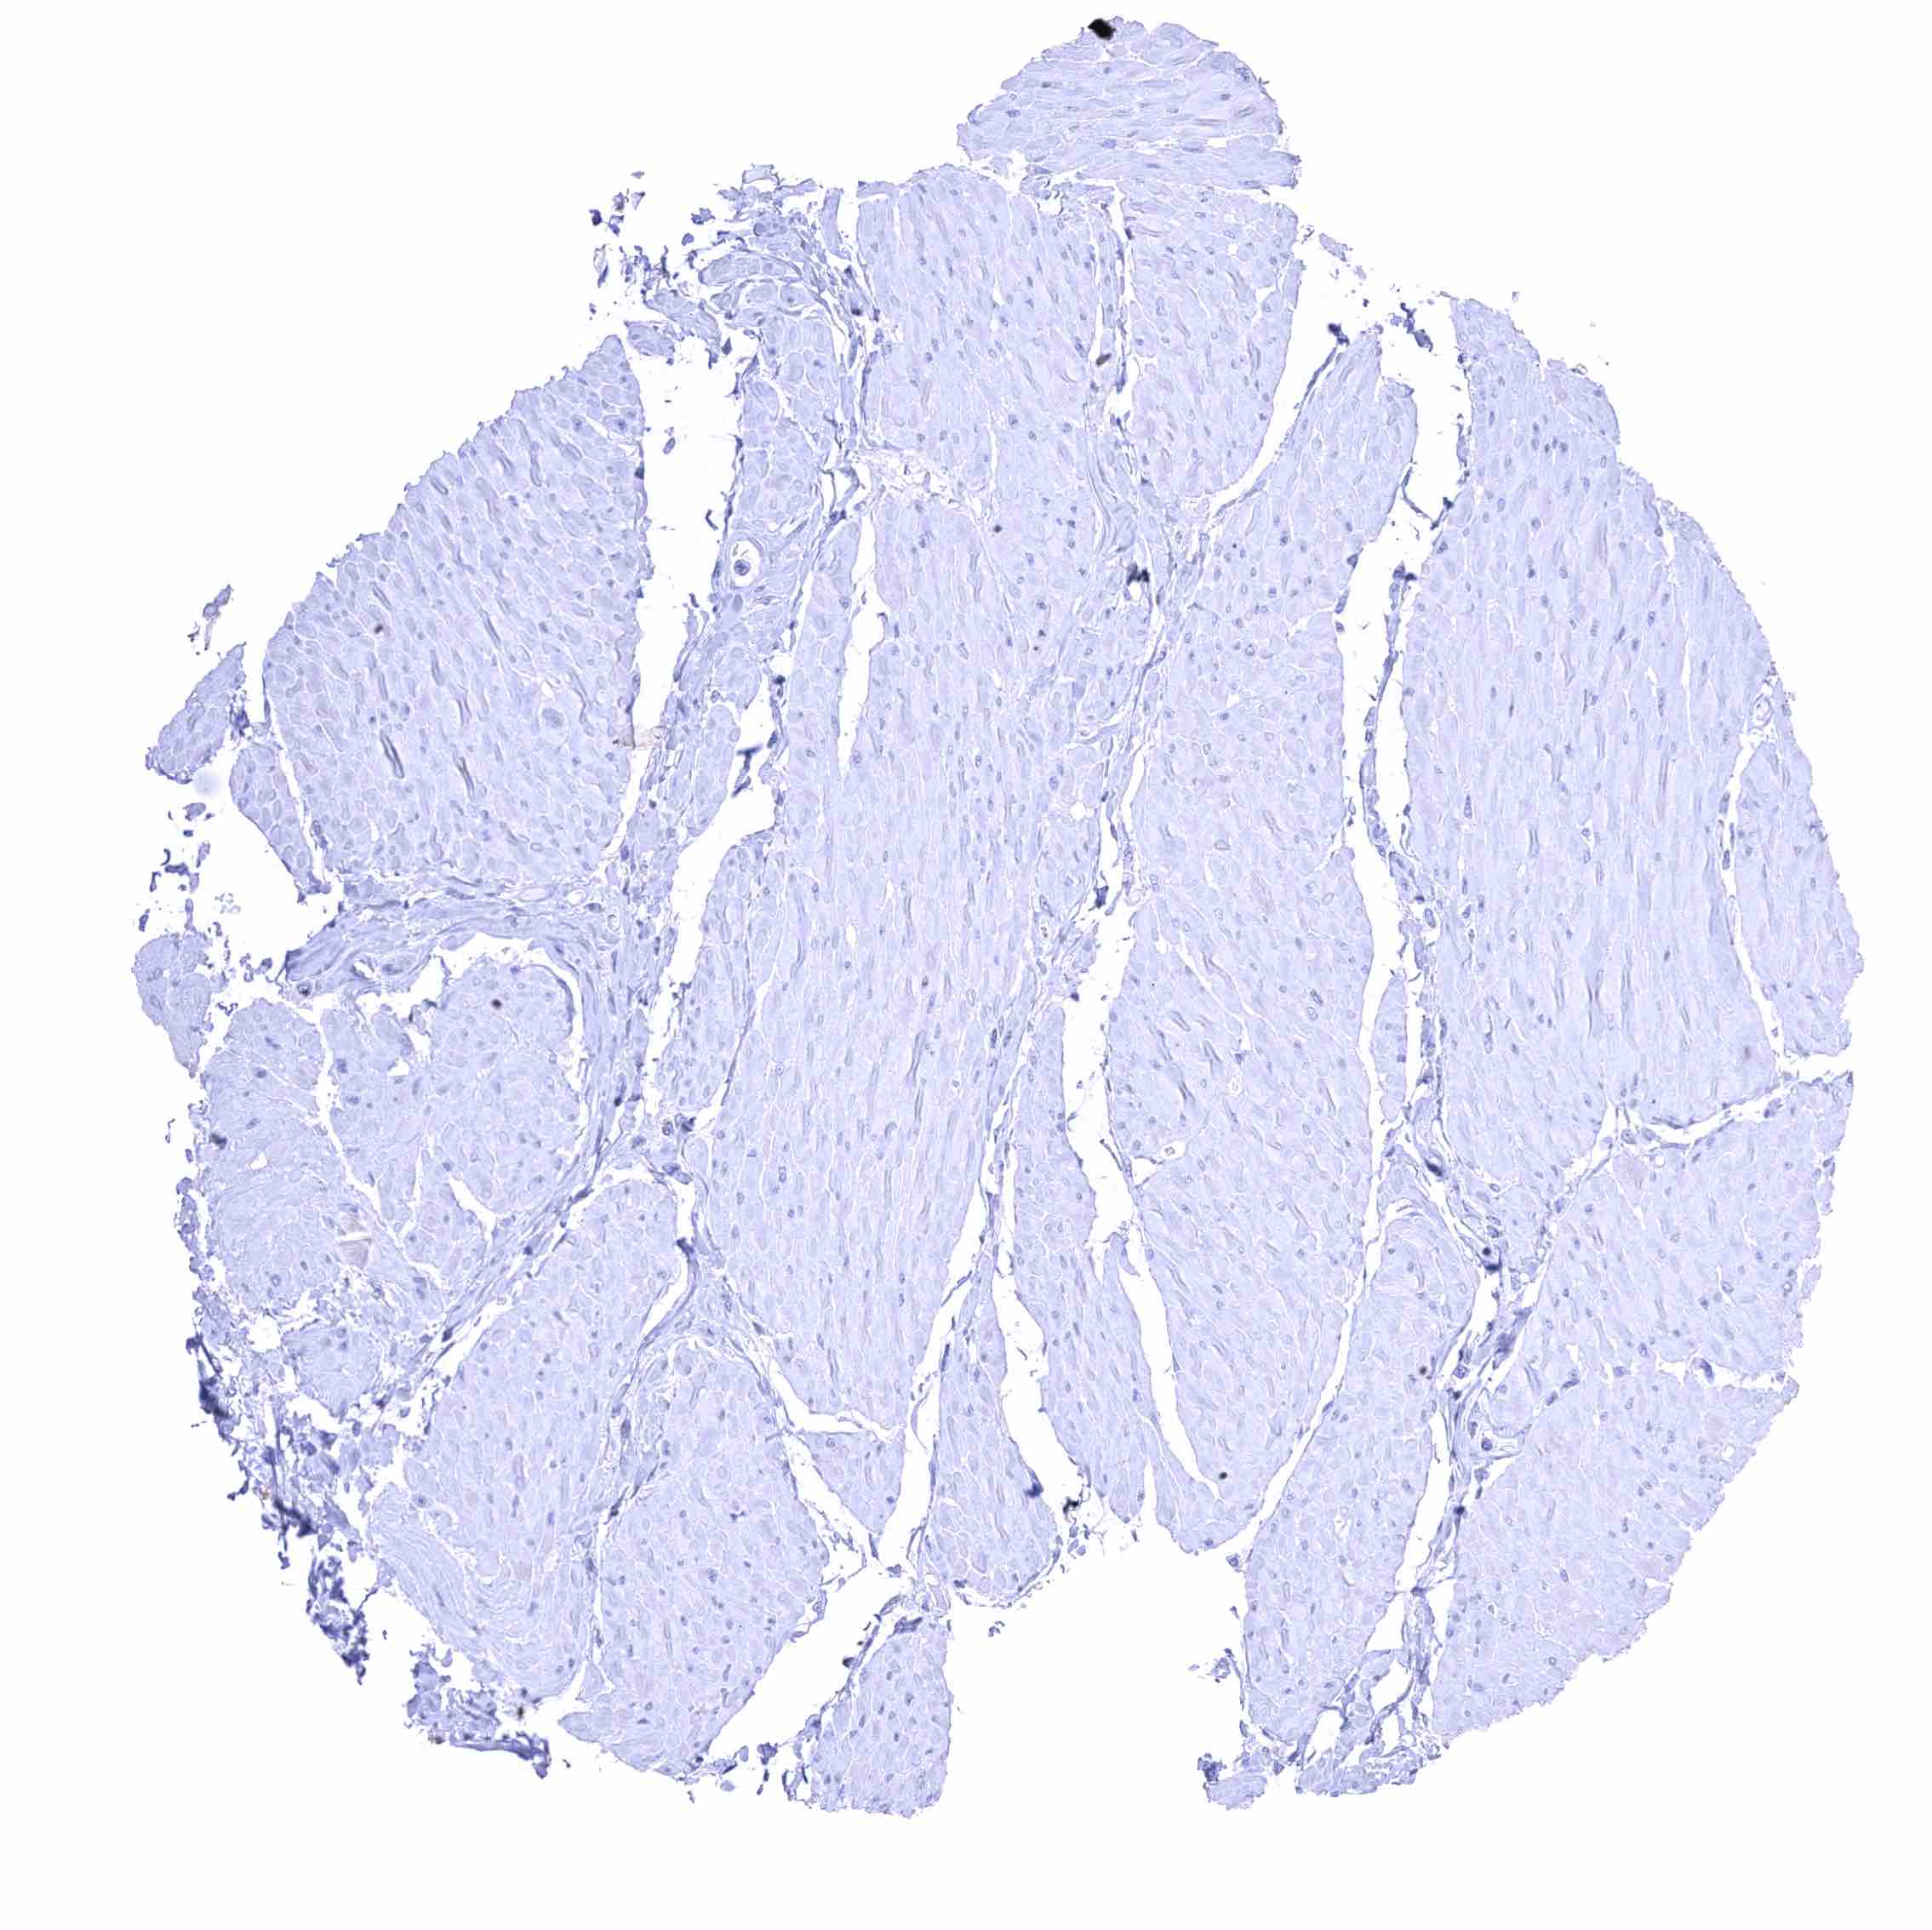

Uterus, ectocervix